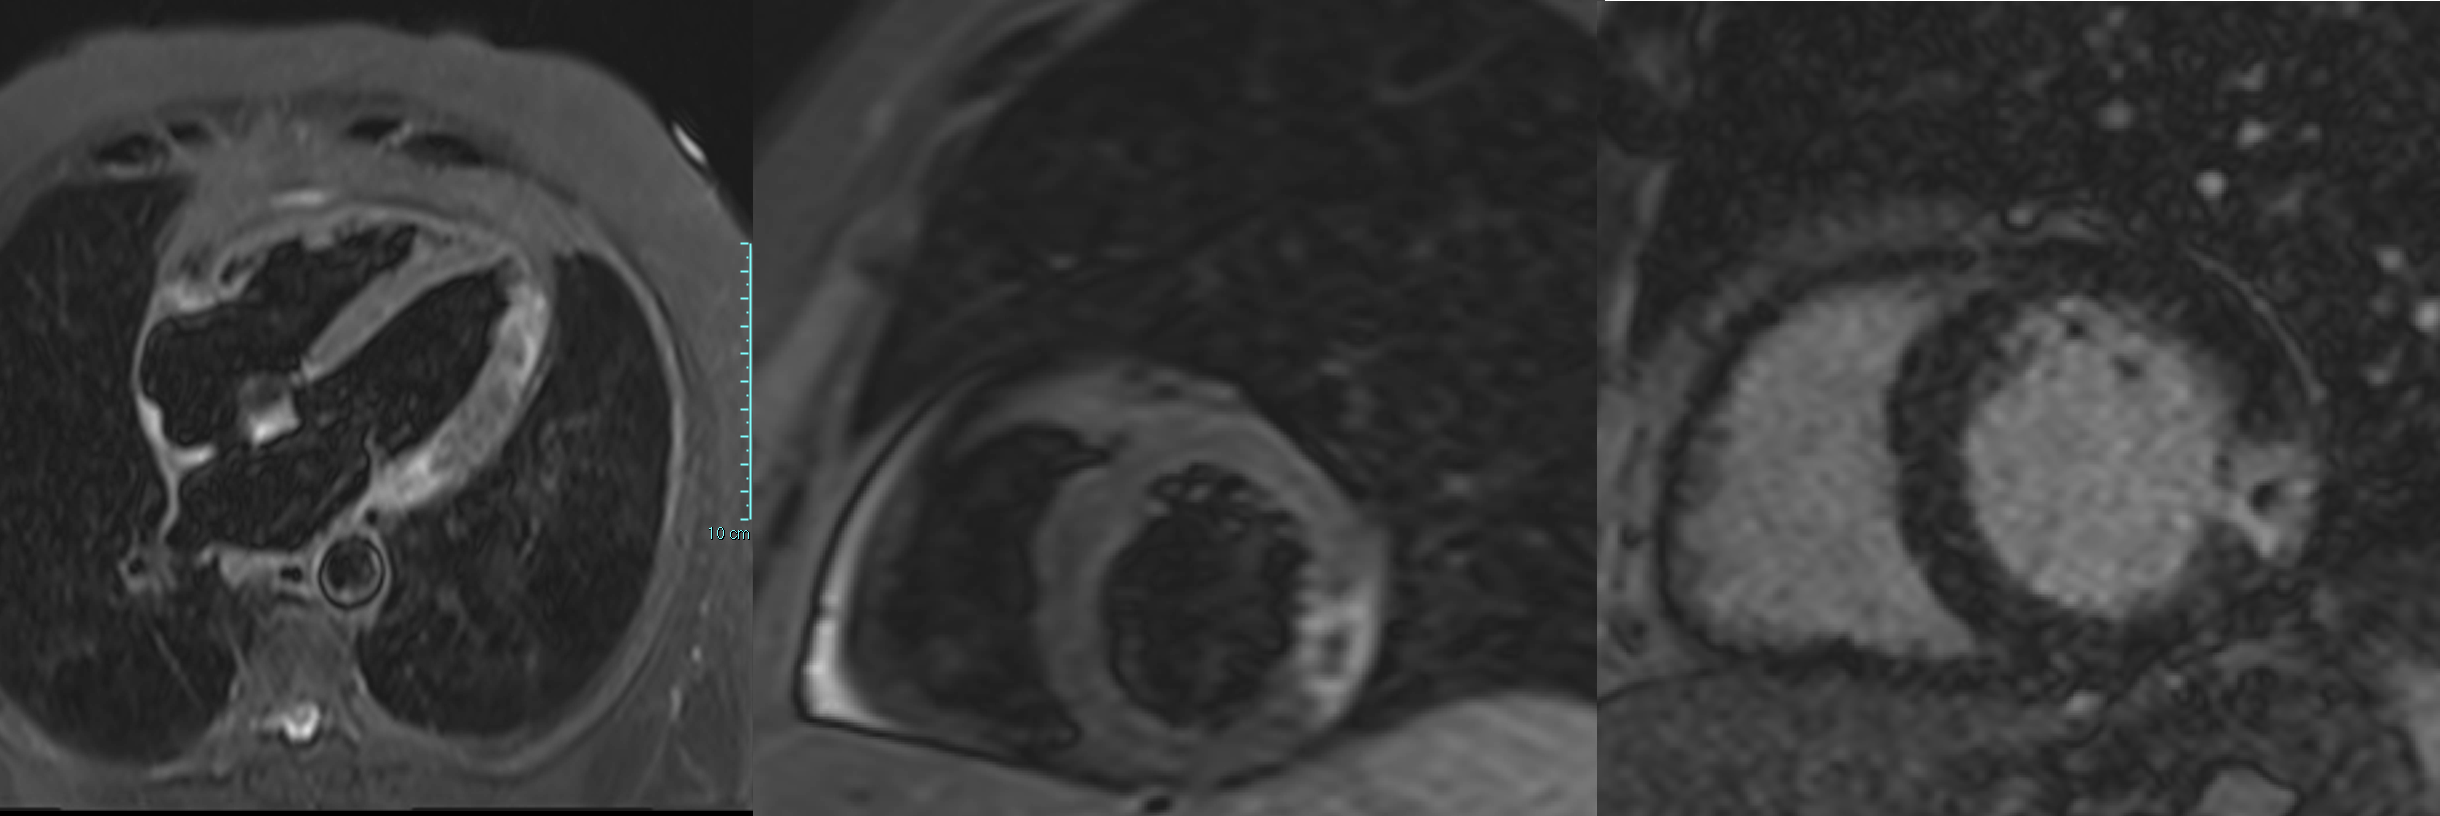

We report the case of a 65-year-old man presenting with chest pain occurring the night before. ECG showed negative T waves in the inferolateral leads. Laboratory revealed rising troponin (0.139 to 0.688 ng/mL). Transthoracic echocardiography demonstrated preserved systolic function without regional wall motion abnormalities (ejection fraction 55%). The day after, complete normalization of the ECG was observed. Patient underwent coronary angiography which revealed an intermediate stenosis of the left anterior descending artery (LAD) not functionally significant (iFR 0.91, FFR 0.87) (Fig. 1). 24-hour Holter ECG monitoring documented episodes of atrial fibrillation. He was discharged on day five with a diagnosis of myocardial infarction with non-obstructive coronary arteries (MINOCA) and referred for cardiac magnetic resonance (CMR). Discharge therapy included Aspirin, Edoxaban and Rosuvastatin/Ezetimibe. Subsequent CMR revealed myocardial edema and late gadolinium enhancement with a transmural ischemic pattern involving the basal inferolateral and anterolateral segments and the apical lateral segment and microvascular obstruction in the basal inferolateral segment, consistent with transmural myocardial infarction (Fig. 2). A subsequent review of the coronary angiogram identified an intermediate, hazy lesion in the proximal circumflex/obtuse marginal branch, compatible with the culprit lesion (Fig. 3). The patient was contacted and clopidogrel 75 mg daily was added, resulting in triple antithrombotic therapy for one month. At 30-day follow-up, the patient remained asymptomatic. This case highlights the pivotal role of CMR in clarifying the diagnosis and guiding therapy in MINOCA, even when the underlying etiology remains uncertain between coronary embolism and unstable plaque.